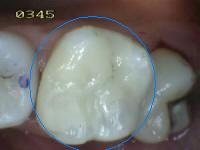

2 |

Sellador completo |